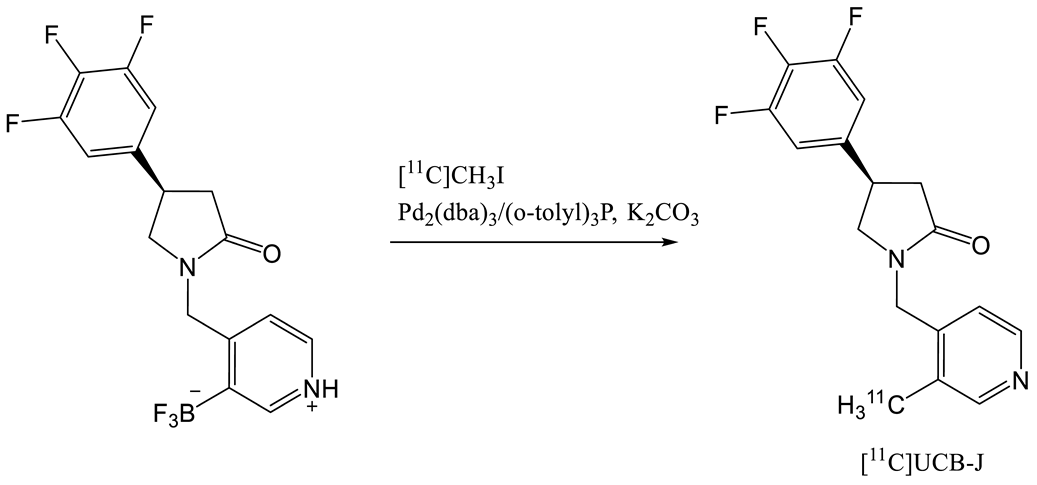

- Nabulsi, N.B.; Mercier, J.; Holden, D.; Carre, S.; Najafzadeh, S.; Vandergeten, M.C.; Lin, S.F.; Deo, A.; Price, N.; Wood, M.; et al. Synthesis and Preclinical Evaluation of 11c-Ucb-J as a Pet Tracer for Imaging the Synaptic Vesicle Glycoprotein 2a in the Brain. J. Nucl. Med. 2016, 57, 777–784. [Google Scholar] [CrossRef] [PubMed] [Green Version]

- Rokka, J.; Schlein, E.; Eriksson, J. Improved synthesis of SV2A targeting radiotracer [11C]UCB-J. EJNMMI Radiopharm. Chem. 2019, 4. [Google Scholar] [CrossRef] [PubMed]

- Sephton, S.M.; Miklovicz, T.; Russell, J.J.; Doke, A.; Li, L.; Boros, I.; Aigbirhio, F.I. Automated radiosynthesis of [11C]UCB-J for imaging synaptic density by positron emission tomography. J. Label. Compd. Radiopharm. 2020, 63, 151–158. [Google Scholar] [CrossRef] [Green Version]

| 5 | [11C]UCB-J | [24] |  | 8.2 | 1.5 | 215 | 35 (dc) |